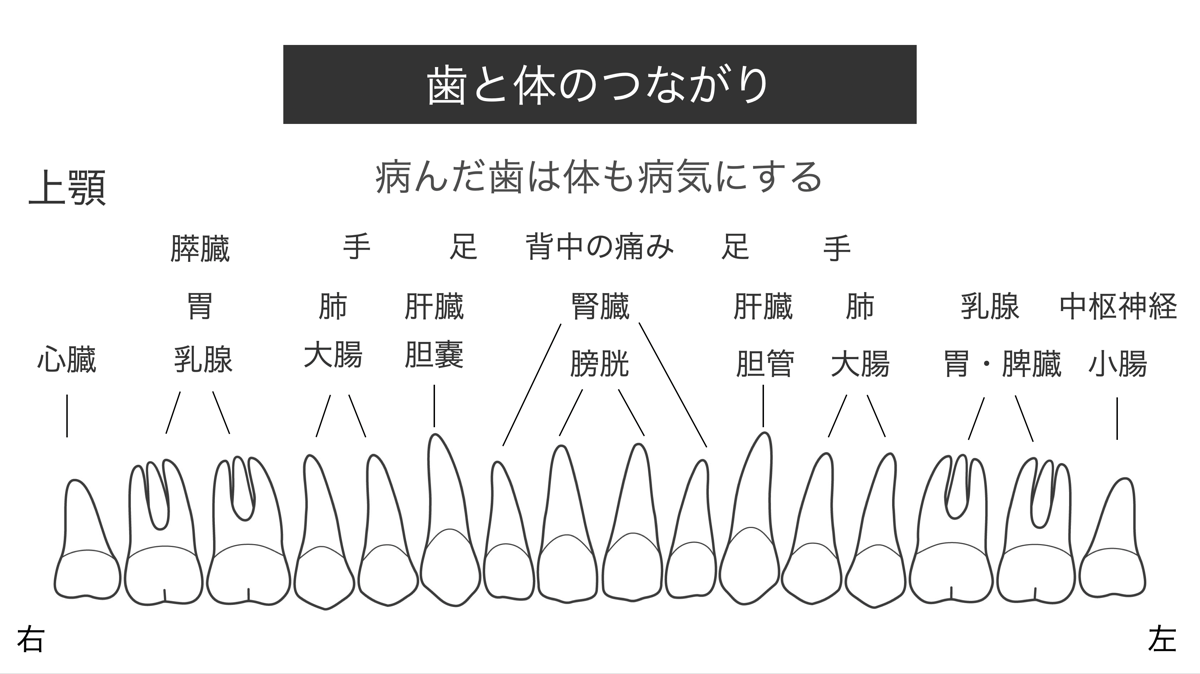

歯と体のつながり

歯は臓器とつながり、歯が病めば臓器も病むと言われます。

下図は一例として上顎の歯と臓器のつながりを示します。例えば、乳腺関連疾患は上顎第一第二大臼歯と、大腸関連疾患は上顎第一第二小臼歯と、それぞれ関連があるとされています。

欧米においては、この歯と臓器のつながりを唱える人が多く、古典中国医学(Traditional Chinese medicine)の経絡の影響を受けています。日本の漢方医学の源流ですが、西洋医学により忘れかけられているように感じます。

民間医療とひどく叱責されることも多いですが、病を抱えている方は一度、歯科医のチェックを受けられるのも良いかもしれません。

下図は一例として上顎の歯と臓器のつながりを示します。例えば、乳腺関連疾患は上顎第一第二大臼歯と、大腸関連疾患は上顎第一第二小臼歯と、それぞれ関連があるとされています。

欧米においては、この歯と臓器のつながりを唱える人が多く、古典中国医学(Traditional Chinese medicine)の経絡の影響を受けています。日本の漢方医学の源流ですが、西洋医学により忘れかけられているように感じます。

民間医療とひどく叱責されることも多いですが、病を抱えている方は一度、歯科医のチェックを受けられるのも良いかもしれません。